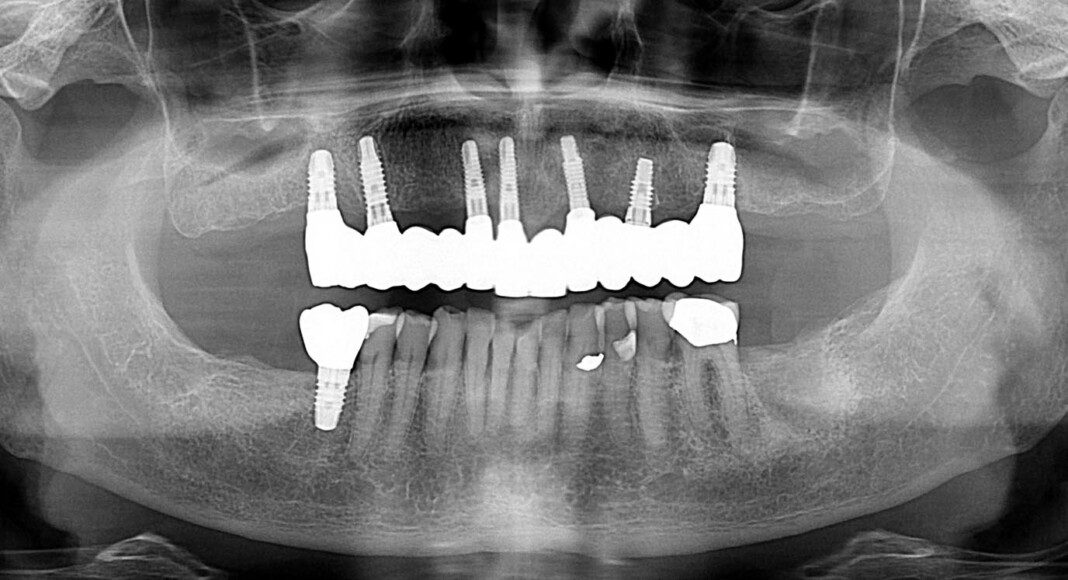

Pre-surgical view after removal of existing restorations. Existing implants were not perfect but reasonable. Better to use them than to try to remove and replace.